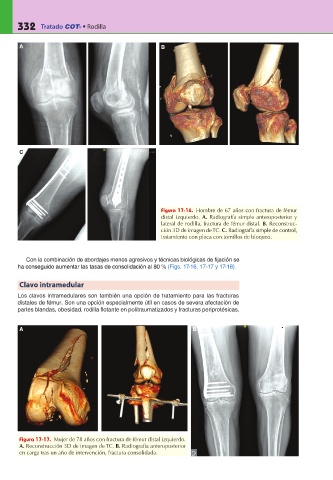

Figura 17-16. Hombre de 67 años con fractura de fémur

distal izquierdo. A. Radiografía simple anteroposterior y

lateral de rodilla, fractura de fémur distal. B. Reconstruc-

ción 3D de imagen de TC. C.

tratamiento con placa con tornillos de bloqueo.

Figura 17-17. Mujer de 78 años con fractura de fémur distal izquierdo.

A. Reconstrucción 3D de imagen de TC. B. Radiografía anteroposterior

en carga tras un año de intervención, fractura consolidada.